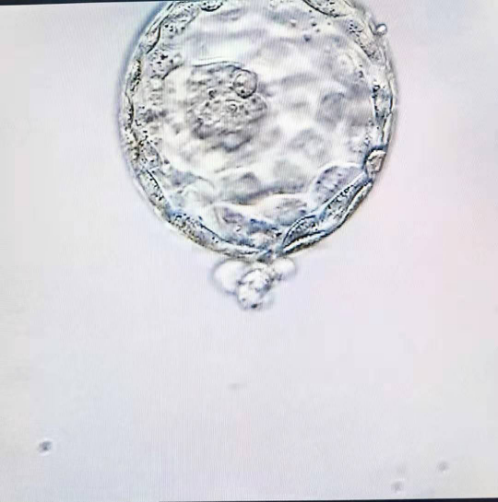

罗女士夫妇自结婚以来多年一直未能怀孕,在家人的焦急等待和期盼下,四处求医未果,承受着巨大的经济和身心压力。去年宫外孕后,更是切除了双侧输卵管,自然妊娠的希望变为零。他们夫妻听说南溪山医院获得了开展试管婴儿技术的资质后,抱着“试试看”的心理来该院就诊。广西壮族自治区南溪山医院辅助生殖科专家组经会诊确认其为双侧输卵管缺如(双侧输卵管切除术后),建议其进行试管婴儿治疗。经过前期的检查和化验,确定了最佳的治疗方案,于2021年1月25日进行了无痛取卵手术,1月28日移植了2枚优质卵裂期胚胎。本次周期,罗女士取卵21枚,正常受精15枚,培养至第三天有10枚优质胚胎,选取了形态最佳的两枚卵裂期胚胎进行移植。冷冻了4枚。剩余的胚胎继续培养,在第5-6天又养成了5枚可利用的囊胚期胚胎,并全部冷冻保存。